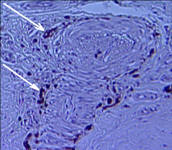

of the Equine Foot

A New 464 Page Textbook, in Full-Color with 630 Pictures and Drawings, by Pete Ramey

A Few Pictures from the book:

Only 570 pictures yet to see... but you get the idea.

Photos referenced in text from Bidwell/Bowker, Bowker, Clayton, Cowles, Hampson, Kellon, Ramey, Ridgway, Sullivan, Taylor, Watts.